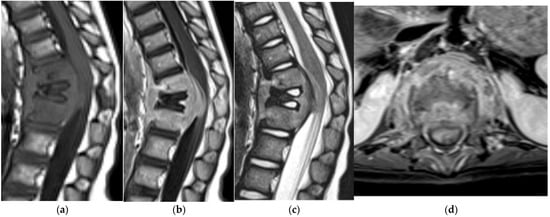

Giant Cell Tumor